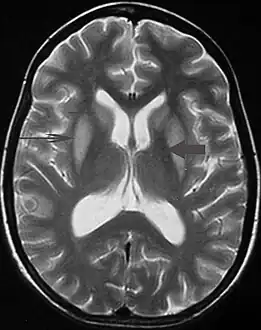

It can be diagnosed clinically in the appropriate context, but may be difficult to confirm radiologically using conventional imaging techniques. Changes are more prominent on MRI than on CT, but often take days or weeks after acute symptom onset to develop. Imaging by MRI typically demonstrates areas of hyperintensity on T2-weighted images.[29]

T2 weighted magnetic resonance scan image showing bilaterally symmetrical hyperintensities in caudate nucleus (small, thin arrow), putamen (long arrow), with sparing of globus pallidus (broad arrow), suggestive of extrapontine myelinolysis (osmotic demyelination syndrome)